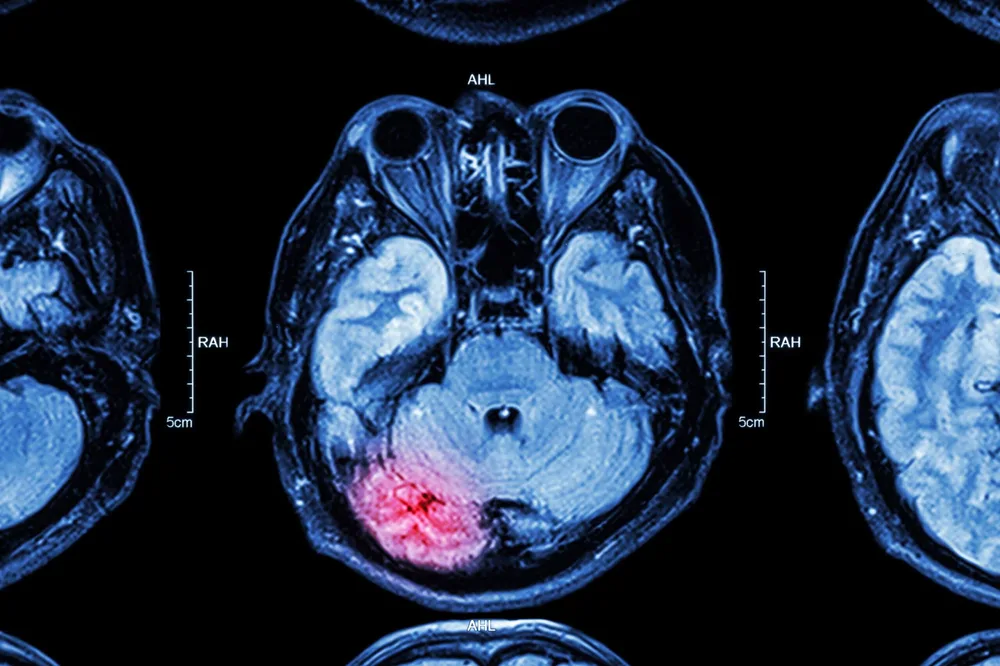

Proving a TBI requires comprehensive medical evidence including diagnostic imaging (MRI, CT scans, DTI), neuropsychological testing results, medical records documenting symptoms and treatment, and expert testimony from neurologists and other specialists. We also present testimony from family members and coworkers who can describe the changes they have observed in the victim's cognitive abilities, personality, and daily functioning.